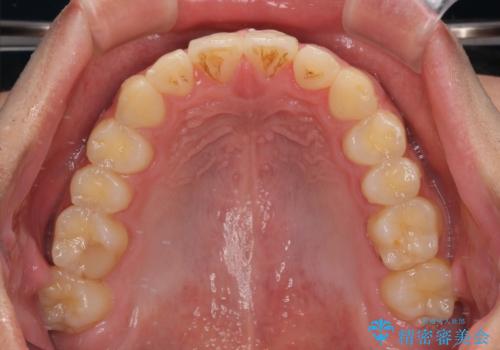

捻れて飛び出した前歯 インビザラインで整った前歯に

歯と歯の間を削ることでうまくスペースコントロールでき、また、毎日22時間以上しっかりとマウスピースを装着していただいたので、スムーズに治療が進みました。

治療途中で転勤となり、遠方からの通院となったため、来院間隔空いてしまいましたが、2年間で終えることができました。